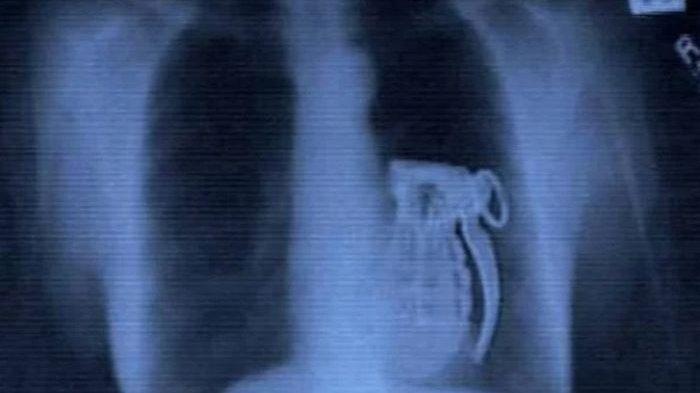

Namun, bersiaplah untuk bergidik, karena dalam daftar ini Anda akan menemukan segalanya mulai dari pisau hingga granat tangan.